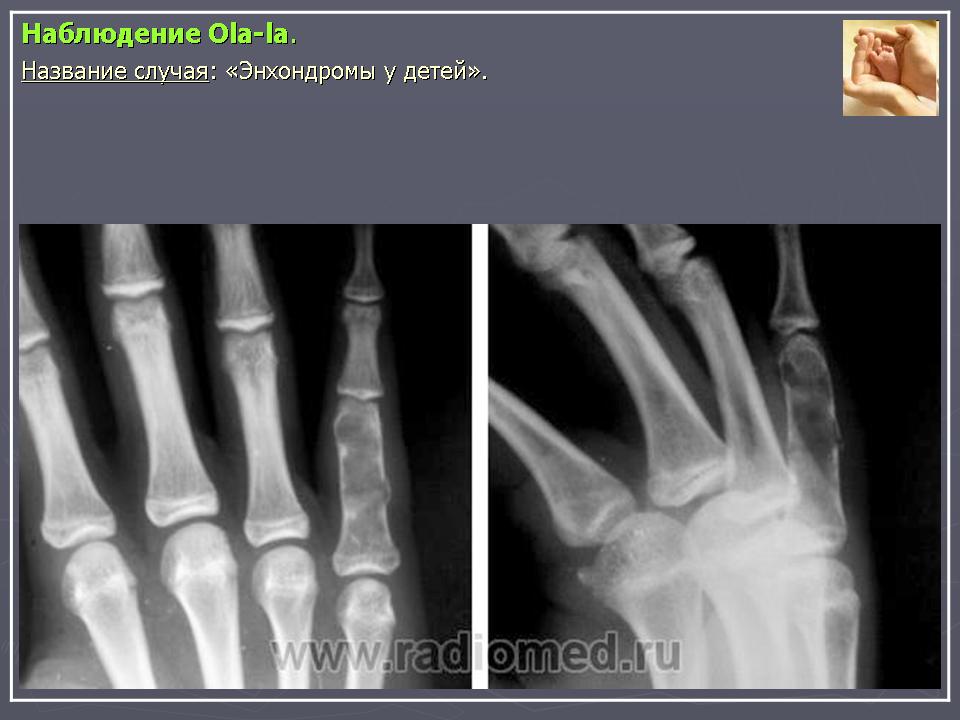

Хондромы являются по морфологическому строению истинными опухолями. Они обладают свойствами присущими опухолям - способностью к прогрессивному росту, рецидивируют. Признаются доброкачественными опухолями, т. к. не метастазируют в отдаленные органы, растут чрезвычайно медленно, нередко годами и даже десятилетиями, заметно не увеличиваясь в размерах. Хотя нет морфологических критериев, которые давали бы основание отличать хондрому одной локализации от другой, локализация в пределах скелета сказывается весьма существенно на клиническом течении хондром. Так, если хондромы коротких трубчатых костей, особенно фаланг кисти не озлокачествляются или озлокачествляются настолько редко, что такие наблюдения описываются как казуистические, то хондромы таза, лопатки, грудины, проксимального отдела бедренной или плечевой костей, озлокачествляются весьма часто. Поэтому больных с хондромами этих локализаций необходимо оперировать также радикально, как и больных с хондросаркомами. Морфологически отдифференцировать хондрому от хондросаркомы высокой степени зрелости нередко затруднительно даже для морфологов высокой квалификации, специально изучающих костную патологию. Подозрение на озлокачествление такого образования может вызвать только четко выраженный рост опухоли, разрушающий окружающую ткань, что наблюдается чрезвычайно редко.

Источником роста хондромы могут явиться нормально расположенный хрящ (суставной, ростковый) и участки дистопированного хряща, а также очаги неокостеневшего эмбрионального хряща. Наиболее часто хондромы встречаются у детей в возрасте 11 -16 лет. Как и все первично-доброкачественные новообразования, хондрома характеризуется солитарным очагом в одной кости. Множественные хондромы, как правило, вторичны и сопровождают диспластический процесс.

Рентгенологическая картина хондромы представляет четко очерченный опухолевый узел. Очаги минерализации в хондромах выглядят достаточно характерно и представлены очаговыми, глыбчатыми или кольцевидными , арочными отложениями извести. Полного разрушения кортикального слоя трубчатой кости с выходом опухолевых масс в мягкие ткани не наблюдается.